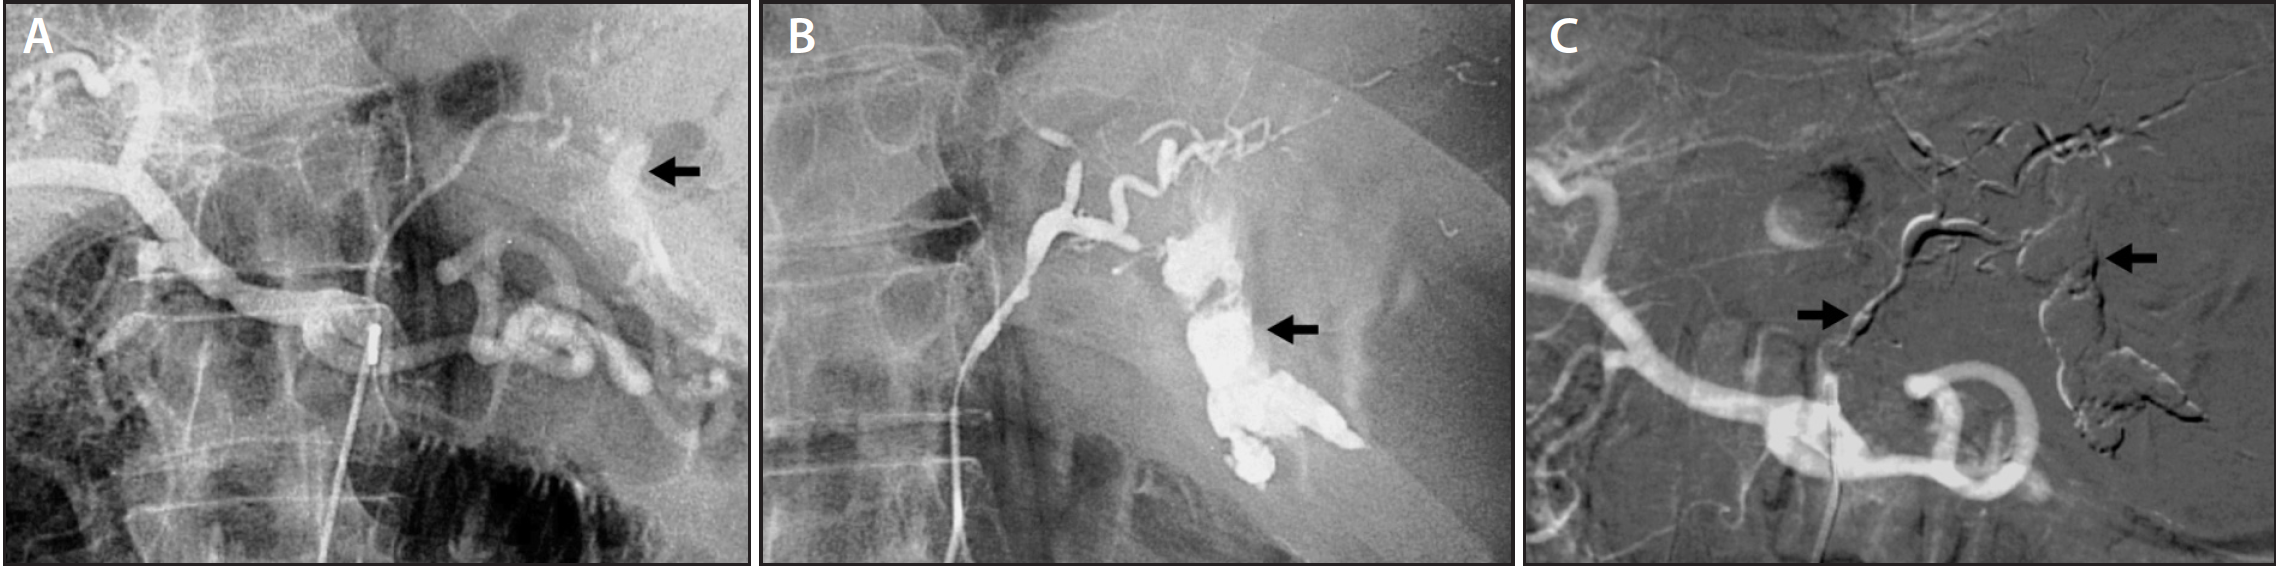

A) Coil embolization is performed to minimize bleeding during Coil Embolization For Gi Bleed — the purpose of this systematic review is to define common clinical practice and clinical and technical outcomes of blind and preventive. selective catheterization for upper gi bleeding should always include the celiac artery and sma. — localized embolization is possible when the bleeding point is superselected. It uses substances (embolic agents) that. — the gastroduodenal. Coil Embolization For Gi Bleed.

Figure 3 from Embolization of Bleeding Duodenal Ulcer Using Amplatzer Coil Embolization For Gi Bleed — the purpose of this systematic review is to define common clinical practice and clinical and technical outcomes of blind and preventive. — localized embolization is possible when the bleeding point is superselected. selective catheterization for upper gi bleeding should always include the celiac artery and sma. an embolization procedure blocks a specific blood vessel to. Coil Embolization For Gi Bleed.